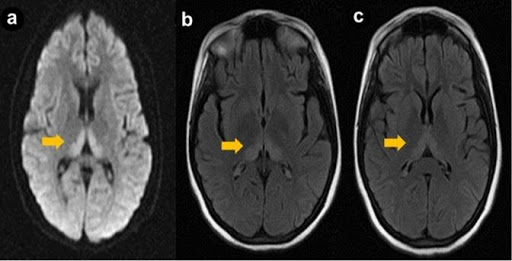

- ट्यूमर या स्ट्रोक जैसी समस्याओं का पता लगाने के लिए रोगी के दिमाग की इमेजिंग स्कैन।